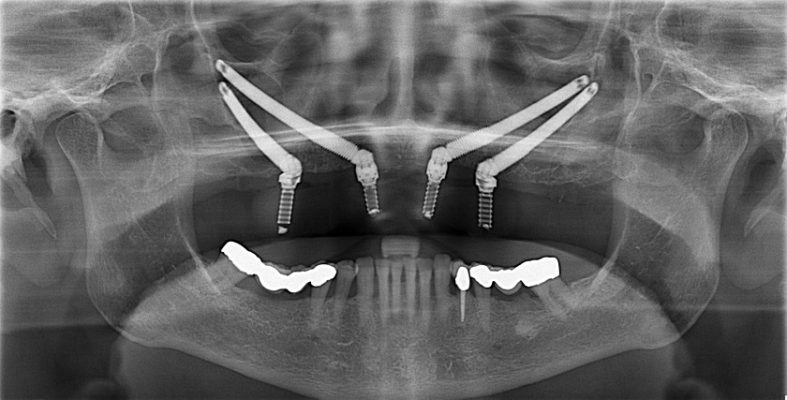

Zygoma Implants hay cấy ghép Implant xương gò má là phương pháp phục hình răng cho bệnh nhân mất răng hàm trên, bị tiêu xương nặng, không thể cấy ghép Implant như thông thường.

Khác biệt lớn nhất của Zygoma Implants là thay vì cấy vào xương hàm thì trụ Implant sẽ được cấy vào xương gò má. Như vậy, trụ Implant sẽ có lộ trình dài hơn, hình dáng thon dài và gấp khúc theo góc độ của vị trí răng mất. Tùy vào từng trường hợp mà bác sĩ sẽ chỉ định cấy 2 hoặc 4 trụ để hỗ trợ cầu răng toàn phần hoặc bán phần.

Đối với phương pháp này, xương gò má đóng vai trò như một cấu trúc nâng đỡ cho răng. Đây được xem là “ánh sáng cuối đường hầm” cho những bệnh nhân mất răng và không đủ điều kiện trồng răng Implant thông thường.

Số lượng trụ Implant tối ưu

Trụ Implant cấy từ xương gò má, được neo chặn ổn định và chắc chắn. Giúp nâng đỡ cấu trúc răng tối ưu mà không cần phải dùng quá nhiều trụ. Ngoài ra còn hạn chế các biến chứng không mong muốn khác như: đào thải trụ Implant, viêm quanh Implant, Implant rơi vào lòng xoang,…